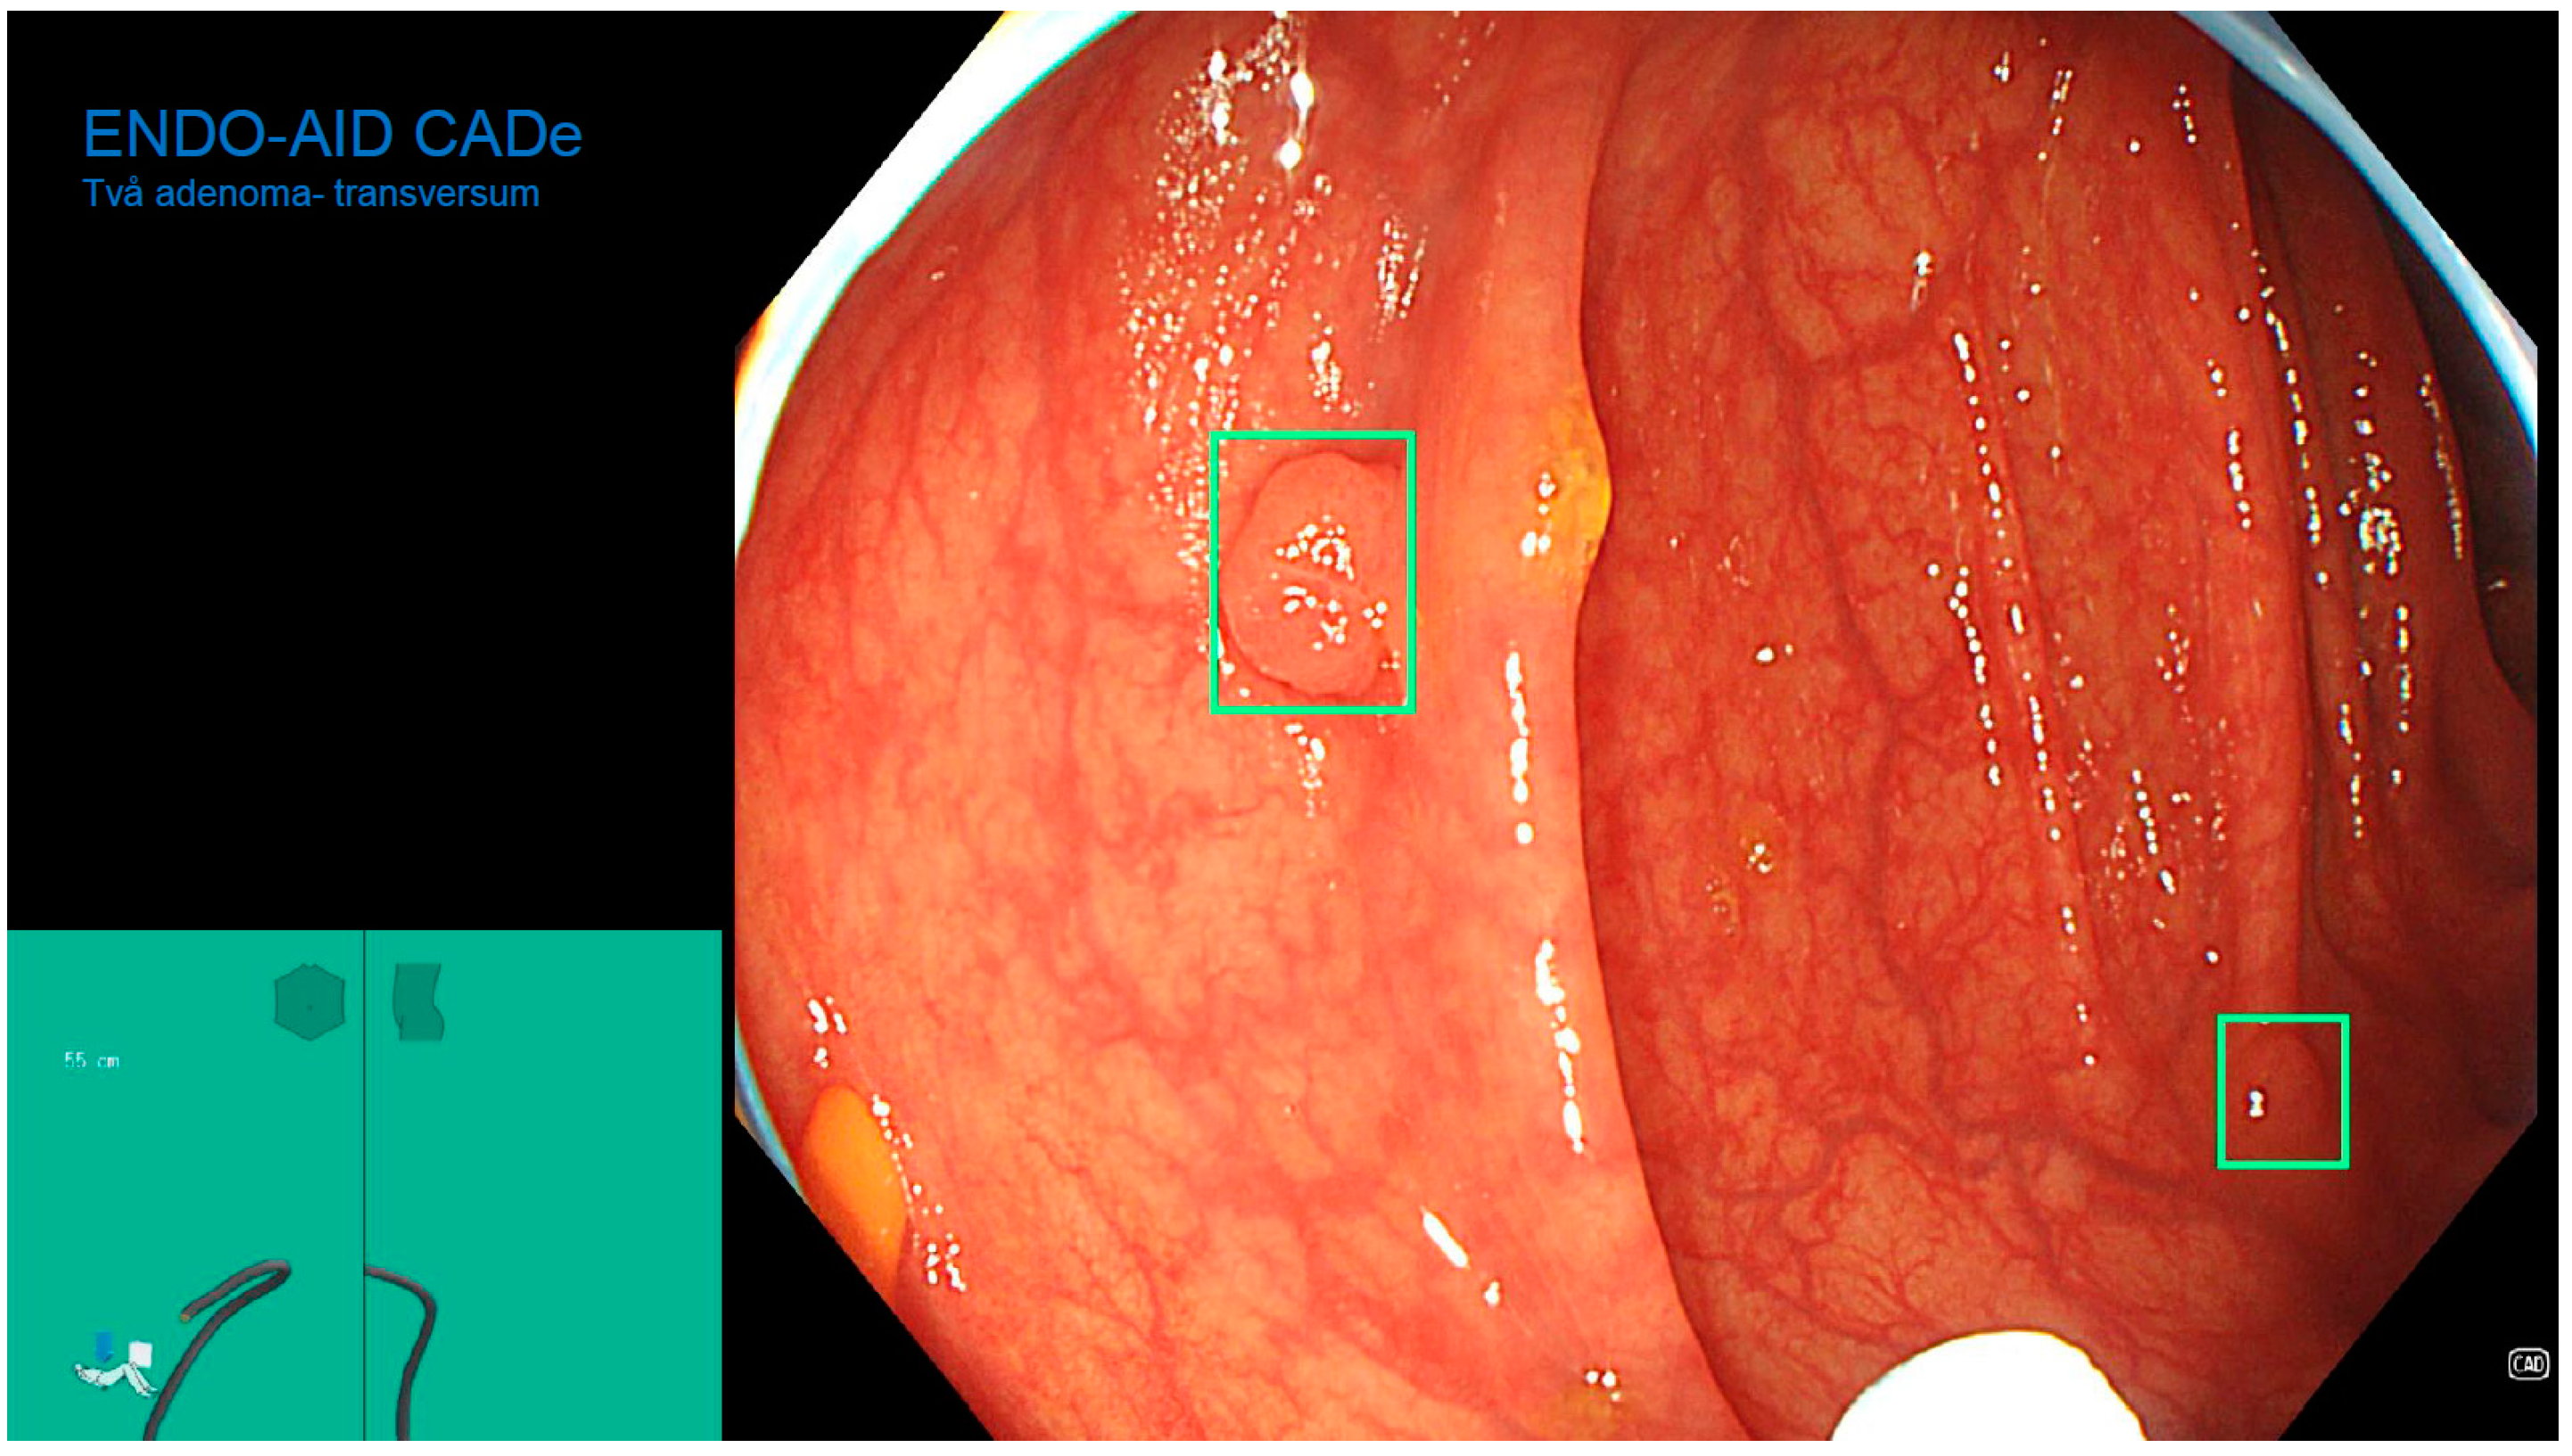

The Role of an Artificial Intelligence Method of Improving the Diagnosis of Neoplasms by Colonoscopy

2. Materials and Methods

2.4. Colonoscopy Procedure